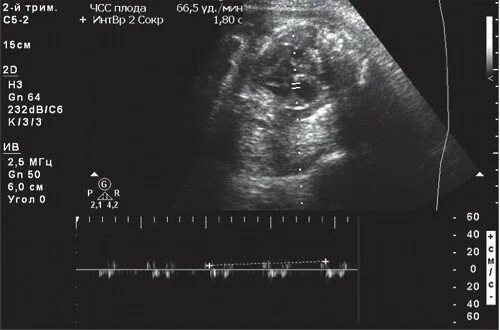

Пульс ребенка в утробе